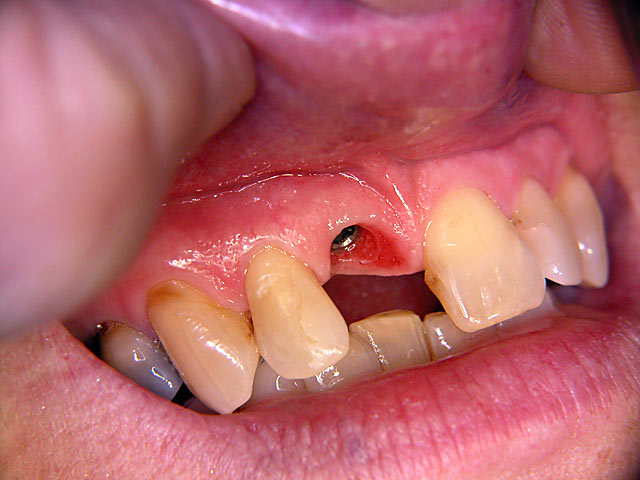

Die folgenden Patientenfälle sollen Ihnen einen Einblick in die Möglichkeiten der modernen Implantation geben.

Frontzahn-Implantation: